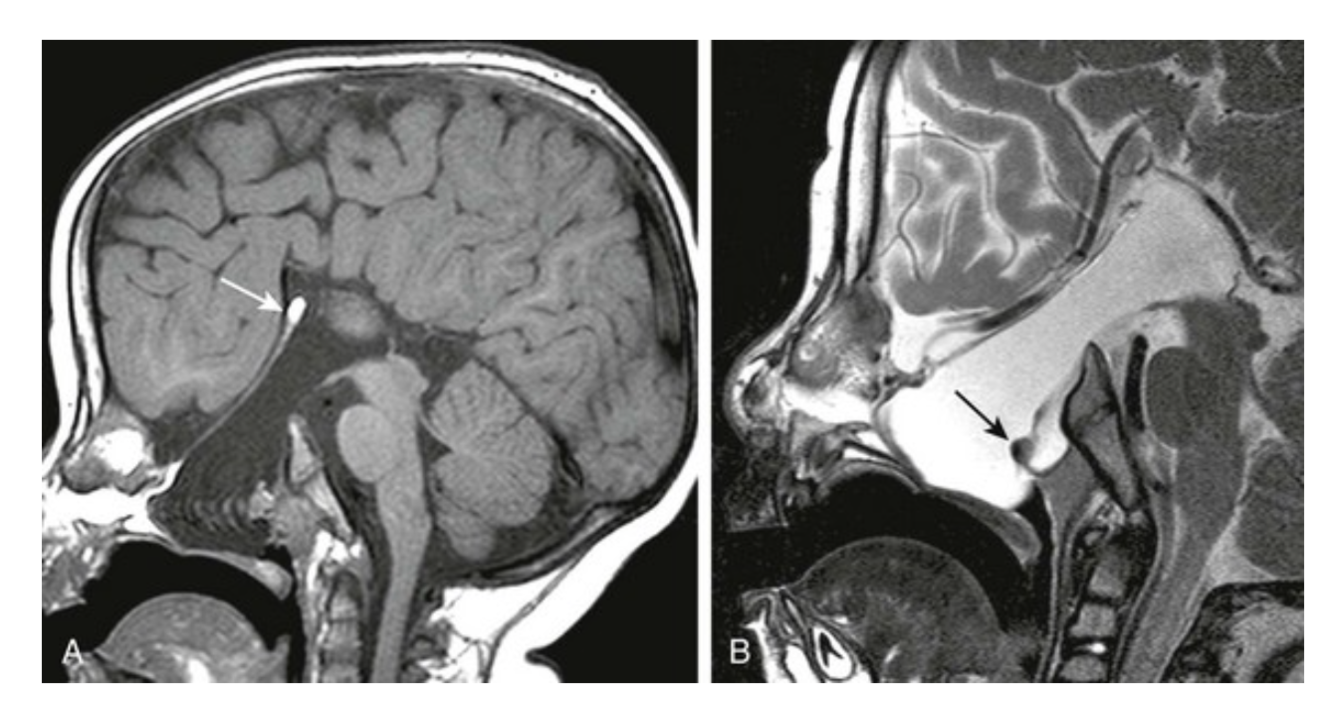

FIGURE 31-5 Basal encephalocele.A, A sagittal T1-weighted image shows callosal agenesis with a tiny lipoma (arrow). A large defect in the basisphenoid is seen. Note the apparent absence of the pituitary, floor of the third ventricle, and optic pathways. B, A high-resolution sagittal T2-weighted image shows the pituitary-hypothalamic structures (arrow) and optic pathways are contained within the encephalocele.